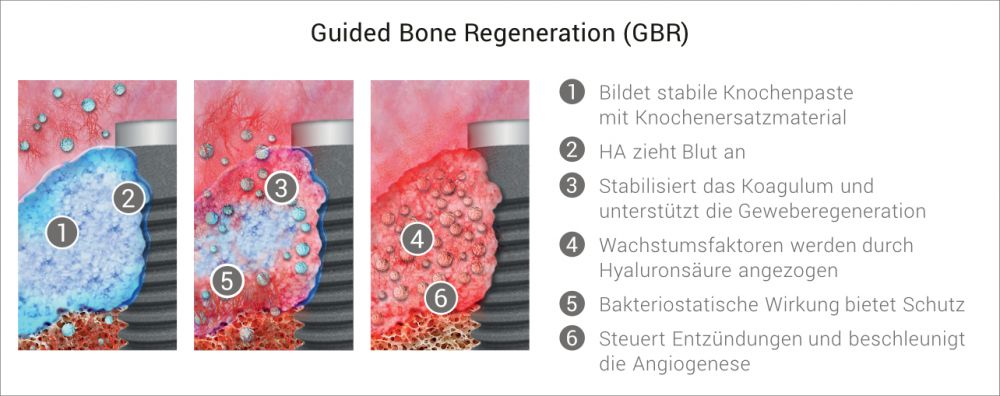

Mit xHyA steht Ihnen eine Hyaluronsäure (HA) zur Verfügung, die für den Einsatz in der regenerativen Zahnmedizin entwickelt wurde.

HA weist eine Reihe von physiologischen Wirkungen auf, die zur Unterstützung der Regeneration von parodontalen und oralen Wunden entscheidend sind, sowohl bei geschlossener als auch bei chirurgischer Anwendung.

- Stabilisierung und Schutz des Wundraums6-11

- Unterstützung der Geweberegeneration9,12-19

- Beschleunigte kontrollierte Wundheilung8,9,20-23

Blutkonzentrate werden heute in der modernen Oralchirurgie stark thematisiert. Sie verbessern das intraoperative Handling von partikulärem KEM („Sticky Bone“) und zeigen positive Effekte auf die Wundheilung.

Aktuellste Publikationen bestätigen die Verbesserung zahlreicher Faktoren bei der Verwendung von Hyaluronsäure in der Knochenregeneration. Das alles in mit einem völlig vereinfachtem Anwendungsprozess ohne Investition.

- Beschleunigte Knochenheilung

- Höhere Volumenstabilität des Augmentats

- Verlängerung des Membran-Abbauprofils

Die zusätzliche Anwesenheit von HA beschleunigte die frühzeitige Neoangiogenese und führte zu einer deutlich verbesserten Knochenqualität, sowohl im apikalen als auch im zentralen Bereich der Alveole.

Aufgrund der oben beschriebenen positiven Eigenschaften von xHyA können signifikant verbesserte Ergebnisse bei Augmentationen erzielt werden.